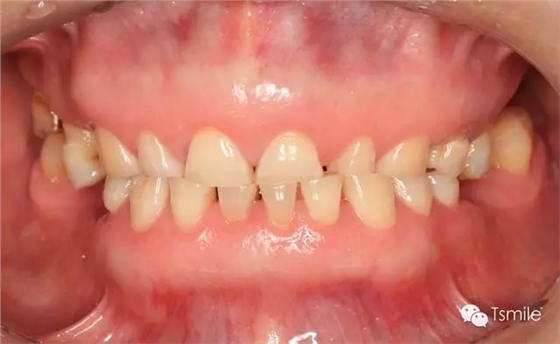

圖1: 夜磨牙導(dǎo)致的牙列重度磨耗

磨耗患者中還有一類特殊的局限于上下前牙區(qū)的牙齒重度磨耗,表現(xiàn)為上前牙舌面、下前牙切端和唇面的重度磨耗。該類患者常表現(xiàn)為一類特殊的咬合類型,重度深覆頜或者上前牙明顯舌傾,這種咬合類型導(dǎo)致下頜前伸功能運(yùn)動(dòng)受限,從而導(dǎo)致前牙區(qū)重度的磨耗,可稱為前牙功能范圍受限(restricted envelope of function)。